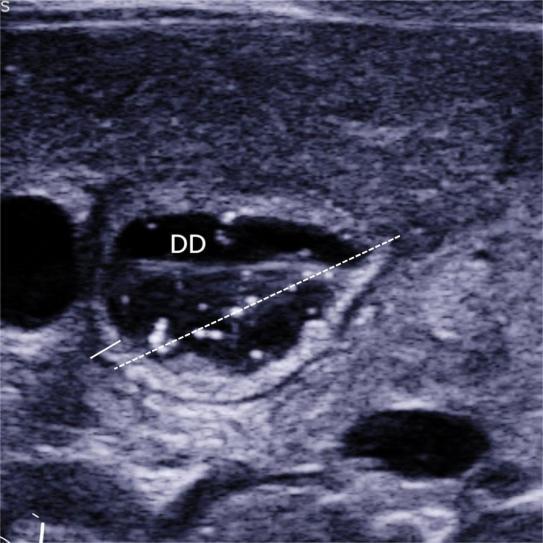

目的 探讨超声参数在新生儿环状胰腺诊断中的应用价值。 方法 收集2016年3月至2018年6月间,于本单位就诊的十二指肠降段梗阻的新生儿56例,均经上消化道超声造影检查。测量超声参数包括十二指肠降段扩张段外径(dilated duodenum diameter, DDD)、十二指肠降段扩张段肠壁厚度(dilated duodenum thickness, DDT)、十二指肠降段狭窄处外径(stenotic duodenum diameter, SDD)。据术中诊断情况分为环状胰腺组(A组)28例、十二指肠降段闭锁组(B组)3例、十二指肠降段隔膜组(C组)25例。采用单因素方差分析比较三组间的三种超声参数差异有无统计学意义,两两比较行LSD-t检验。如两两比较差异均有统计学意义,采用受试者工作特征曲线计算通过超声参数来诊断环状胰腺的曲线下面积及最佳截点值。 结果 三组中的DDD分别为(23.2 ± 2.4)、(25 ± 1.0)、(19.4 ± 2.6)mm,三组比较显示差异有统计学意义(F = 19.406,P < 0.001),两两比较显示A组、B组与C组相比,差异有统计学意义(t = 5.7,P < 0.05;t = 3.793,P < 0.05);A组与B组相比差异无统计学意义(t = 1.232,P > 0.05)。三组DDT分别为(3.0 ± 0.6)、(3.2 ± 0.4)、(2.4 ± 0.3)mm,三组比较显示差异有统计学意义(F = 12.487,P < 0.001),两两比较显示A组、B组与C组相比,差异有统计学意义(t = 4.695,P < 0.05;t = 2.778,P < 0.05),A组与B组相比,差异无统计学意义(t = 0.666,P > 0.05);三组中的SDD分别为(1.9 ± 0.3)、(3.6 ± 0.8)、(5.5 ± 0.7)mm,三组比较显示差异有统计学意义(F = 333.556,P < 0.001),两两比较,显示差异均有统计学意义(t = 5.521,P < 0.05;t = 6.142,P < 0.05;t = 25.828,P < 0.05)。采用SDD ≤ 2.3 mm来诊断环状胰腺的敏感性、特异性、阳性预测值、阴性预测值分别为96.4%、100%、100%、96.6%,曲线下面积为0.999。 结论 SDD可用于诊断新生儿环状胰腺。

Objective To investigate the clinical utility of ultrasound parameters in diagnosing neonatal annular pancreas. Methods A total of 56 neonates with descending duodenal obstruction underwent saline?contrast ultrasound examination. Ultrasonic parameters, including dilated duodenum diameter (DDD), dilated duodenum thickness (DDT), and stenosis duodenum diameter (SDD), were measured. The cases were categorized into three groups: annular pancreas (group A, n = 28), descending duodenal atresia (group B, n = 3), and descending duodenal septum (group C, n = 25). One?way ANOVA was employed to compare statistical differences among the three ultrasonic parameters across the groups, followed by LSD?t test for pairwise comparisons between two groups showing significant differences. Receiver operating characteristics analysis was conducted to calculate the area under the curve and determine the cut?off value if there were statistically significant differences observed. Results In group A, group B, group C, the diameters of DDD were measured as(23.2 ± 2.4)mm, (25 ± 1.0)mm, (19.4 ± 2.6)mm, respectively. When comparing these three groups, there was a statistically significant difference between group A or group B and group C in terms of DDD diameter measurements (t = 5.7, P < 0.05; t = 3.793, P < 0.05). However, no statistically significant difference was observed between group A and group B for DDD diameter measurements (t = 1.232, P > 0.05). The corresponding values for DDT were measured as (3.0 ± 0.6)mm, (3.2 ± 0.4) mm,and(2.4 ± 0.3) mm,respectively. When comparing these three groups,the results showed a statistically significant difference between either Group A or Group B compared to Group C in terms of DDT measurement (t = 4.695, P < 0.05; t = 2.778, P < 0.05). However,no statistically significant difference was found between Group A and Group B regarding the measurement of DDT (t = 0.666, P > 0.05). The SDD measurements in the three groups were (1.9 ± 0.3) mm, (3.6 ± 0.8)mm, (5.5 ± 0.7)mm, respectively. Statistical analysis using LSD?t test revealed significant differences between the three groups (t = 5.521, P < 0.05; t = 6.142, P < 0.05; t = 25.828, P < 0.05).The sensitivity, specificity, positive predictive value, and negative predictive value for detecting annular pancreas at a cutoff of 2.3 mm were determined to be 96.4%, 100%, 100%, and 96.6%, respectively, with an area under the receiver operating characteristic curve of 0.999. Conclusion SDD could be employed for the diagnosis of neonatal annular pancreas.